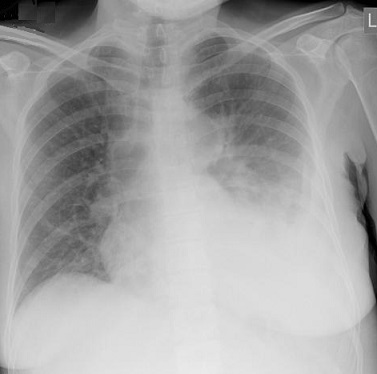

Image de pleuresie

pulmonaire le plus souvent a gauche |